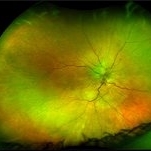

Disseminated Chorioretinitis With Unknown Etiology

Disseminated Chorioretinitis With Unknown Etiology

Apr 5 2018 by Kim Barrett

Ultra-wide field fluorescein angiogram of a 31-year-old female with intermittent pain in her left eye. Her condition has been managed in Liberia until recently when she moved to the United States. She suffers from multiple modalities including central retinal artery occlusion, posterior synechiae of the iris, interstitial keratitis, disseminated chorioretinitis, as well as HIV. An infectious cause is high on the differential in light of her HIV status. DDx: hypertensive crisis, an embolism (? IV drug use), coagulopathy, trauma, infectious. Blood work was normal. Her current vision is 20/30 right eye and 20/400 left eye.

Photographer: Kim Barrett, COA

Imaging device: Optos

Condition/keywords: central retinal artery occlusion (CRAO), chorioretinal scar, ciliary artery sparring, disseminated chorioretinitis, HIV, left eye, optic atrophy, staining